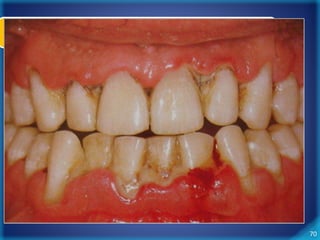

Periodontite Crônica

• Características Clássicas

– Inflamação gengival

– Sangramento à sondagem

– Redução da resistência tecidual

– Perda de inserção gengival

– Perda de tecido ósseo alveolar

– Recessões gengivais

67